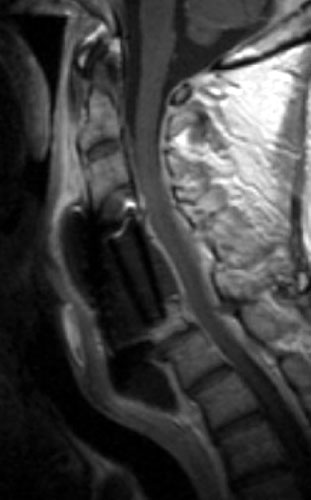

A B C Sagittal T2 FSE (A), sagittal T1 pre (B) and post contrast administration (C) show the graft with blooming artifact where the plate exists anteriorly as well as the screw (lower portion of the image). The susceptibility artifact of the screw shows its ventral positioning essentially outside of the C7 vertebral body. Also, there is T2 hyperintense fluid surrounding the surgical site with the graft material is now surrounded by nonenhancing mixed signal intensity material, predominately hypointense on T1 and hyperintense on T2, possibly suggesting some blood products. There is enhancement in both the anterior and posterior epidural spaces. The distal end of the fixation plate with the screw in the C6 vertebral body appears now displaced anteriorly and there is significant prevertebral soft tissue swelling. Also, this fluid- like material surrounding the bone graft appears to cause some narrowing of the spinal canal, with some mild spinal canal stenosis.